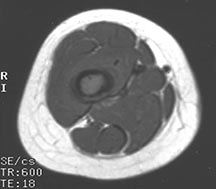

- May arise from any bone and any site within a bone (epiphyseal, metaphyseal, diaphyseal)

- Radiographically variable appearance: may appear benign (geographic) or malignant (permeative or moth eaten)

- Femur